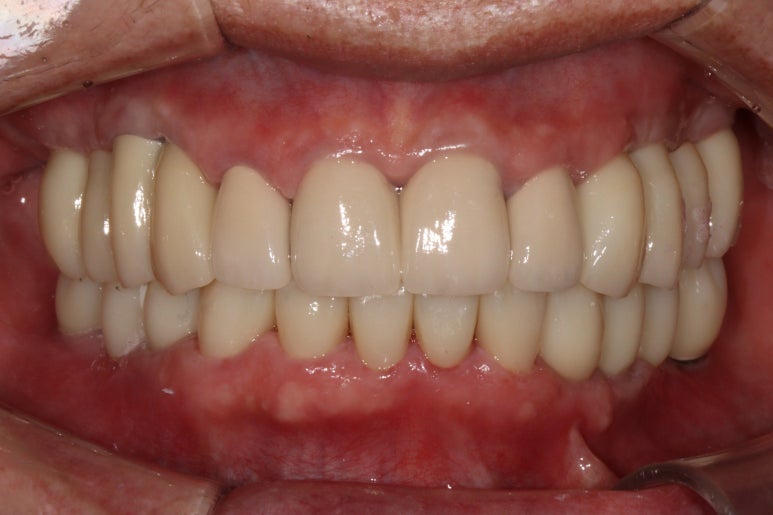

Before & After!!

마지막 뚜둔! 비포 앤 애프터 시간이죠?

솔직히 제가 봐도 미라클한 최종 치료 사진...

이렇게 잘해도 되는건가요..!!!

적절한 색조와 형태를 가진 앞니 보철물.. 그리고 적절히 기능하도록 설정된 아래턱의 위치

모든것이 조화롭게 완성된 치료 후 구강내 사진입니다.

환자분도 정말 너무너무 대만족 하셨어요 :)